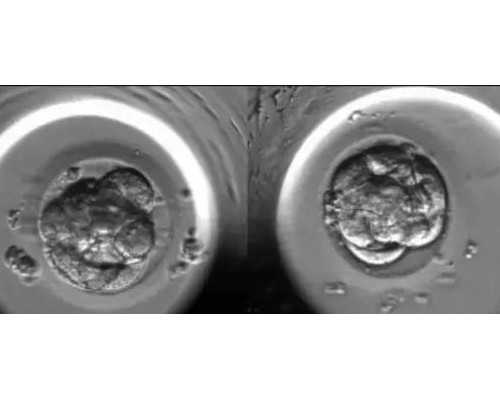

香港检查是经过查验母亲血液判别胎儿性其他办法,抽取孕妈妈手臂静脉血液大约12ML做检查,在母血里分别出胎儿的游离DNA,检查DNA里是不是包括有Y染色体基因,发现有Y染色体基因,就是男宝宝,相反就是女宝宝。上面咱们提到母体和女宝宝是不具备Y基因的,除非是在怀有男宝的情况下。香港验血查性别,孕七周就可以做,可靠性高,归于无创性检测,避免流产的风险,准确率高达99.4% 以上。

香港验血技术也可以说现在现已抵达了世界一流水平,其科学根据就是:孕妈妈的血液标本被抽出后,首要经过两次高速离心处理,将上层的清液移入新的无菌管内,冷冻保存备用。然后运用试剂将上清液中的DNA提取出来,将其染色,放在在紫外灯下查询。假设看到SRY的条带意味着是男孩,没有则标明是女孩。

1、咱们都知道每个常人的身体内有23对染色体,其间22对为男女所共有的染色体,称之为常染色体,其他一对是抉择了性其他染色体,男女各有不同,称为性染色体,男性的为XY,女性的为XX。

2、这就是说,女性的基因组中性染色体组合必定为XX,没有Y染色体,所以要是在孕妈妈的血液中检测到有Y染色体上特有的基因片段,那么几乎就可以断定怀的是男胎,要是孕妈妈血液中没有检测到Y染色体,就说明是女胎。